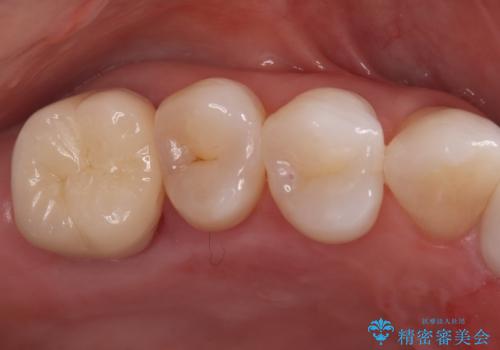

オールセラミッククラウンによる修復: 根管内が清潔に封鎖されたことを確認した後、土台を立てて歯の形を整えました。最終的な被せ物には、金属を一切使用しないオールセラミッククラウンを選択。天然歯のような透明感を再現し、高い適合性によって再び虫歯になるリスクを抑えています。

今回の治療により、詰め物が取れた根本的な原因が解消され、見た目も美しく、長持ちする奥歯を再建することができました。